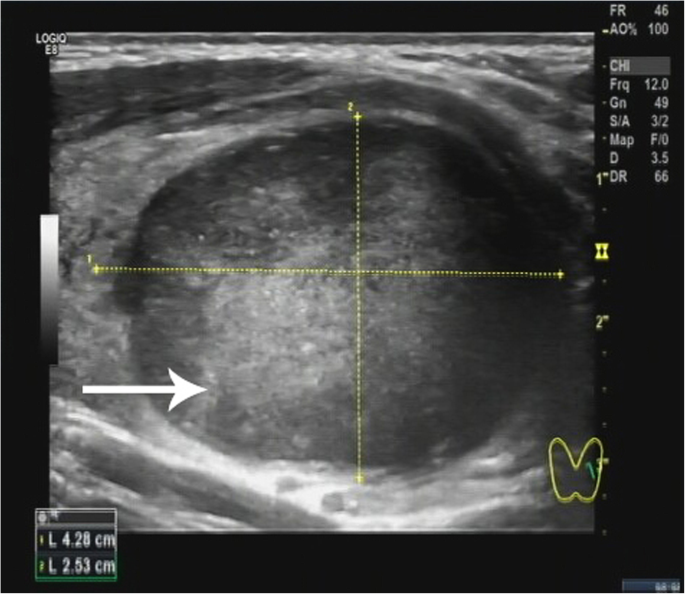

A 34-year-old Chinese woman presented with a painless neck mass that had persisted for over a month. Physical examination on admission revealed a solid nodule with a clear boundary, measuring approximately 4 cm, in the left lobe of the thyroid. The serum levels of thyroglobulin were high (180.3 ng/mL, normal reference range: 3.5–77 ng/mL), as were the levels of anti-thyroglobulin antibodies (529.7 IU/mL, normal reference range: 0–115 IU/mL). Other indices of thyroid function were normal. Ultrasonography revealed a hypoechoic mass, 4.28 × 2.53 cm in size, in the left lobe of the thyroid gland. The mass showed clear boundaries and a rich blood flow signal (Fig. 1). Fine-needle aspiration biopsy revealed that it could be an inflammatory hyperplastic lesion, and a left lobectomy was performed subsequently. During surgery, a solid mass, 5 × 3 cm2 in size, was observed in the middle of the left lobe of the thyroid. The mass had a smooth surface and clear boundaries, and there was no break in the thyroid capsule.